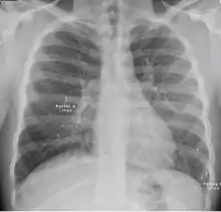

Chest X-ray

A posterior-anterior (PA) chest X-ray is the standard view used; other views (lateral or lordotic) or CT scans may be necessary.

In active pulmonary TB, infiltrates or consolidations and/or cavities are often seen in the upper lungs with or without mediastinal or hilar lymphadenopathy.[1] However, lesions may appear anywhere in the lungs. In HIV and other immunosuppressed persons, any abnormality may indicate TB or the chest X-ray may even appear entirely normal.[1]

Old healed tuberculosis usually presents as pulmonary nodules in the hilar area or upper lobes, with or without fibrotic scars and volume loss.[1] Bronchiectasis and pleural scarring may be present.

Nodules and fibrotic scars may contain slowly multiplying tubercle bacilli with the potential for future progression to active tuberculosis.[1] Persons with these findings, if they have a positive tuberculin skin test reaction, should be considered high-priority candidates for treatment of latent infection regardless of age. Conversely, calcified nodular lesions (calcified granuloma) pose a very low risk for future progression to active tuberculosis.

Abnormalities on chest radiographs may be suggestive of, but are never diagnostic of, TB.[1] However, if a person has a positive response to the tuberculin skin test and no symptoms of the disease, chest radiographs can be used to rule out the possibility of pulmonary TB.